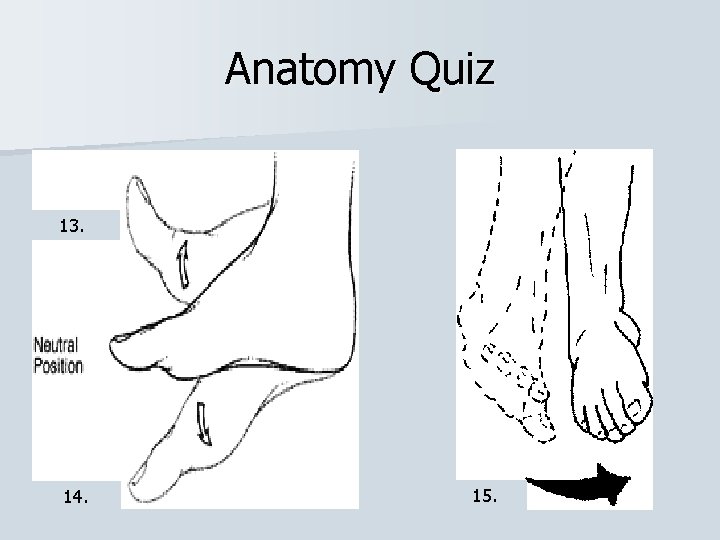

Actions of the Ankle Joint Supination Pronation

Anatomy Quiz 13. 14. 15.